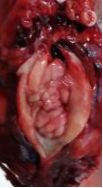

廣泛開展腹腔鏡下腎癌根治術(shù)、腎盂癌根治術(shù)、腎部分切除術(shù)、腎腫瘤剜除術(shù)、腎上腺腫瘤切除術(shù)、腎盂輸尿管成形術(shù)、腎囊腫去頂減壓術(shù)、輸尿管上段切開取石術(shù)等。全腔鏡下進(jìn)行,創(chuàng)傷小、恢復(fù)快。

腹腔鏡腎腫瘤剜除術(shù)(保腎) 腹腔鏡腎癌根治術(shù) 腹腔鏡腎盂癌根治術(shù)